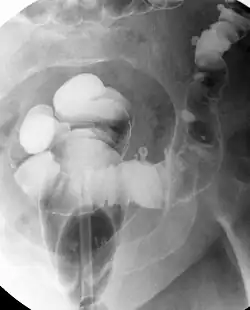

Die Divertikulose ist eine Veränderung des Dickdarms in Form von kleinen Ausstülpungen der Darmwand. Bei diesen Ausstülpungen wird von falschen Divertikeln gesprochen. Falsch werden sie genannt, da hier im Gegensatz zu den echten Divertikeln nur die Schleimhaut und nicht die ganze Darmwand ausgestülpt wird.

Die Diagnose wird entweder endoskopisch oder häufig als Zufallsbefund im Rahmen einer Computertomografie des Abdomens gestellt.